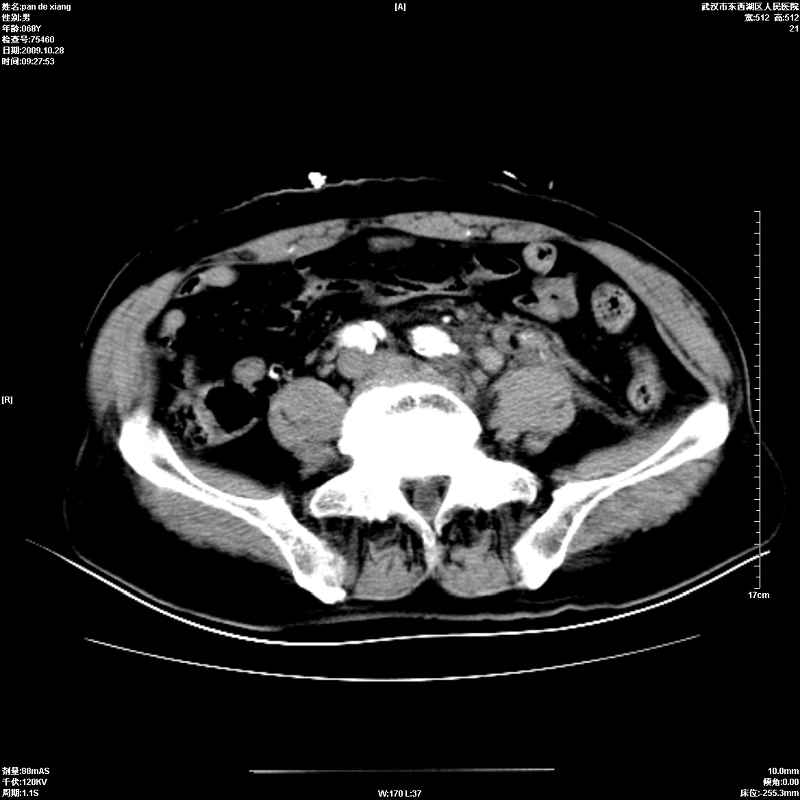

以下是引用杀毒软件在2009-10-28 20:41:00的发言:[br]结合临床考虑---白血病双肾改变或淋巴瘤。

以下是引用zxl51642在2009-10-29 9:59:00的发言:[br]结合临床“单克隆免疫球蛋白血症”,考虑双肾为继发损害并肾功能不全(尿中大量igg及少量iga、igm等大分子免疫球蛋白滤出所致继发损害),椎前软组织肿块为髓外造血。与浆细胞瘤有区别,平扫时有战友说的很清楚。